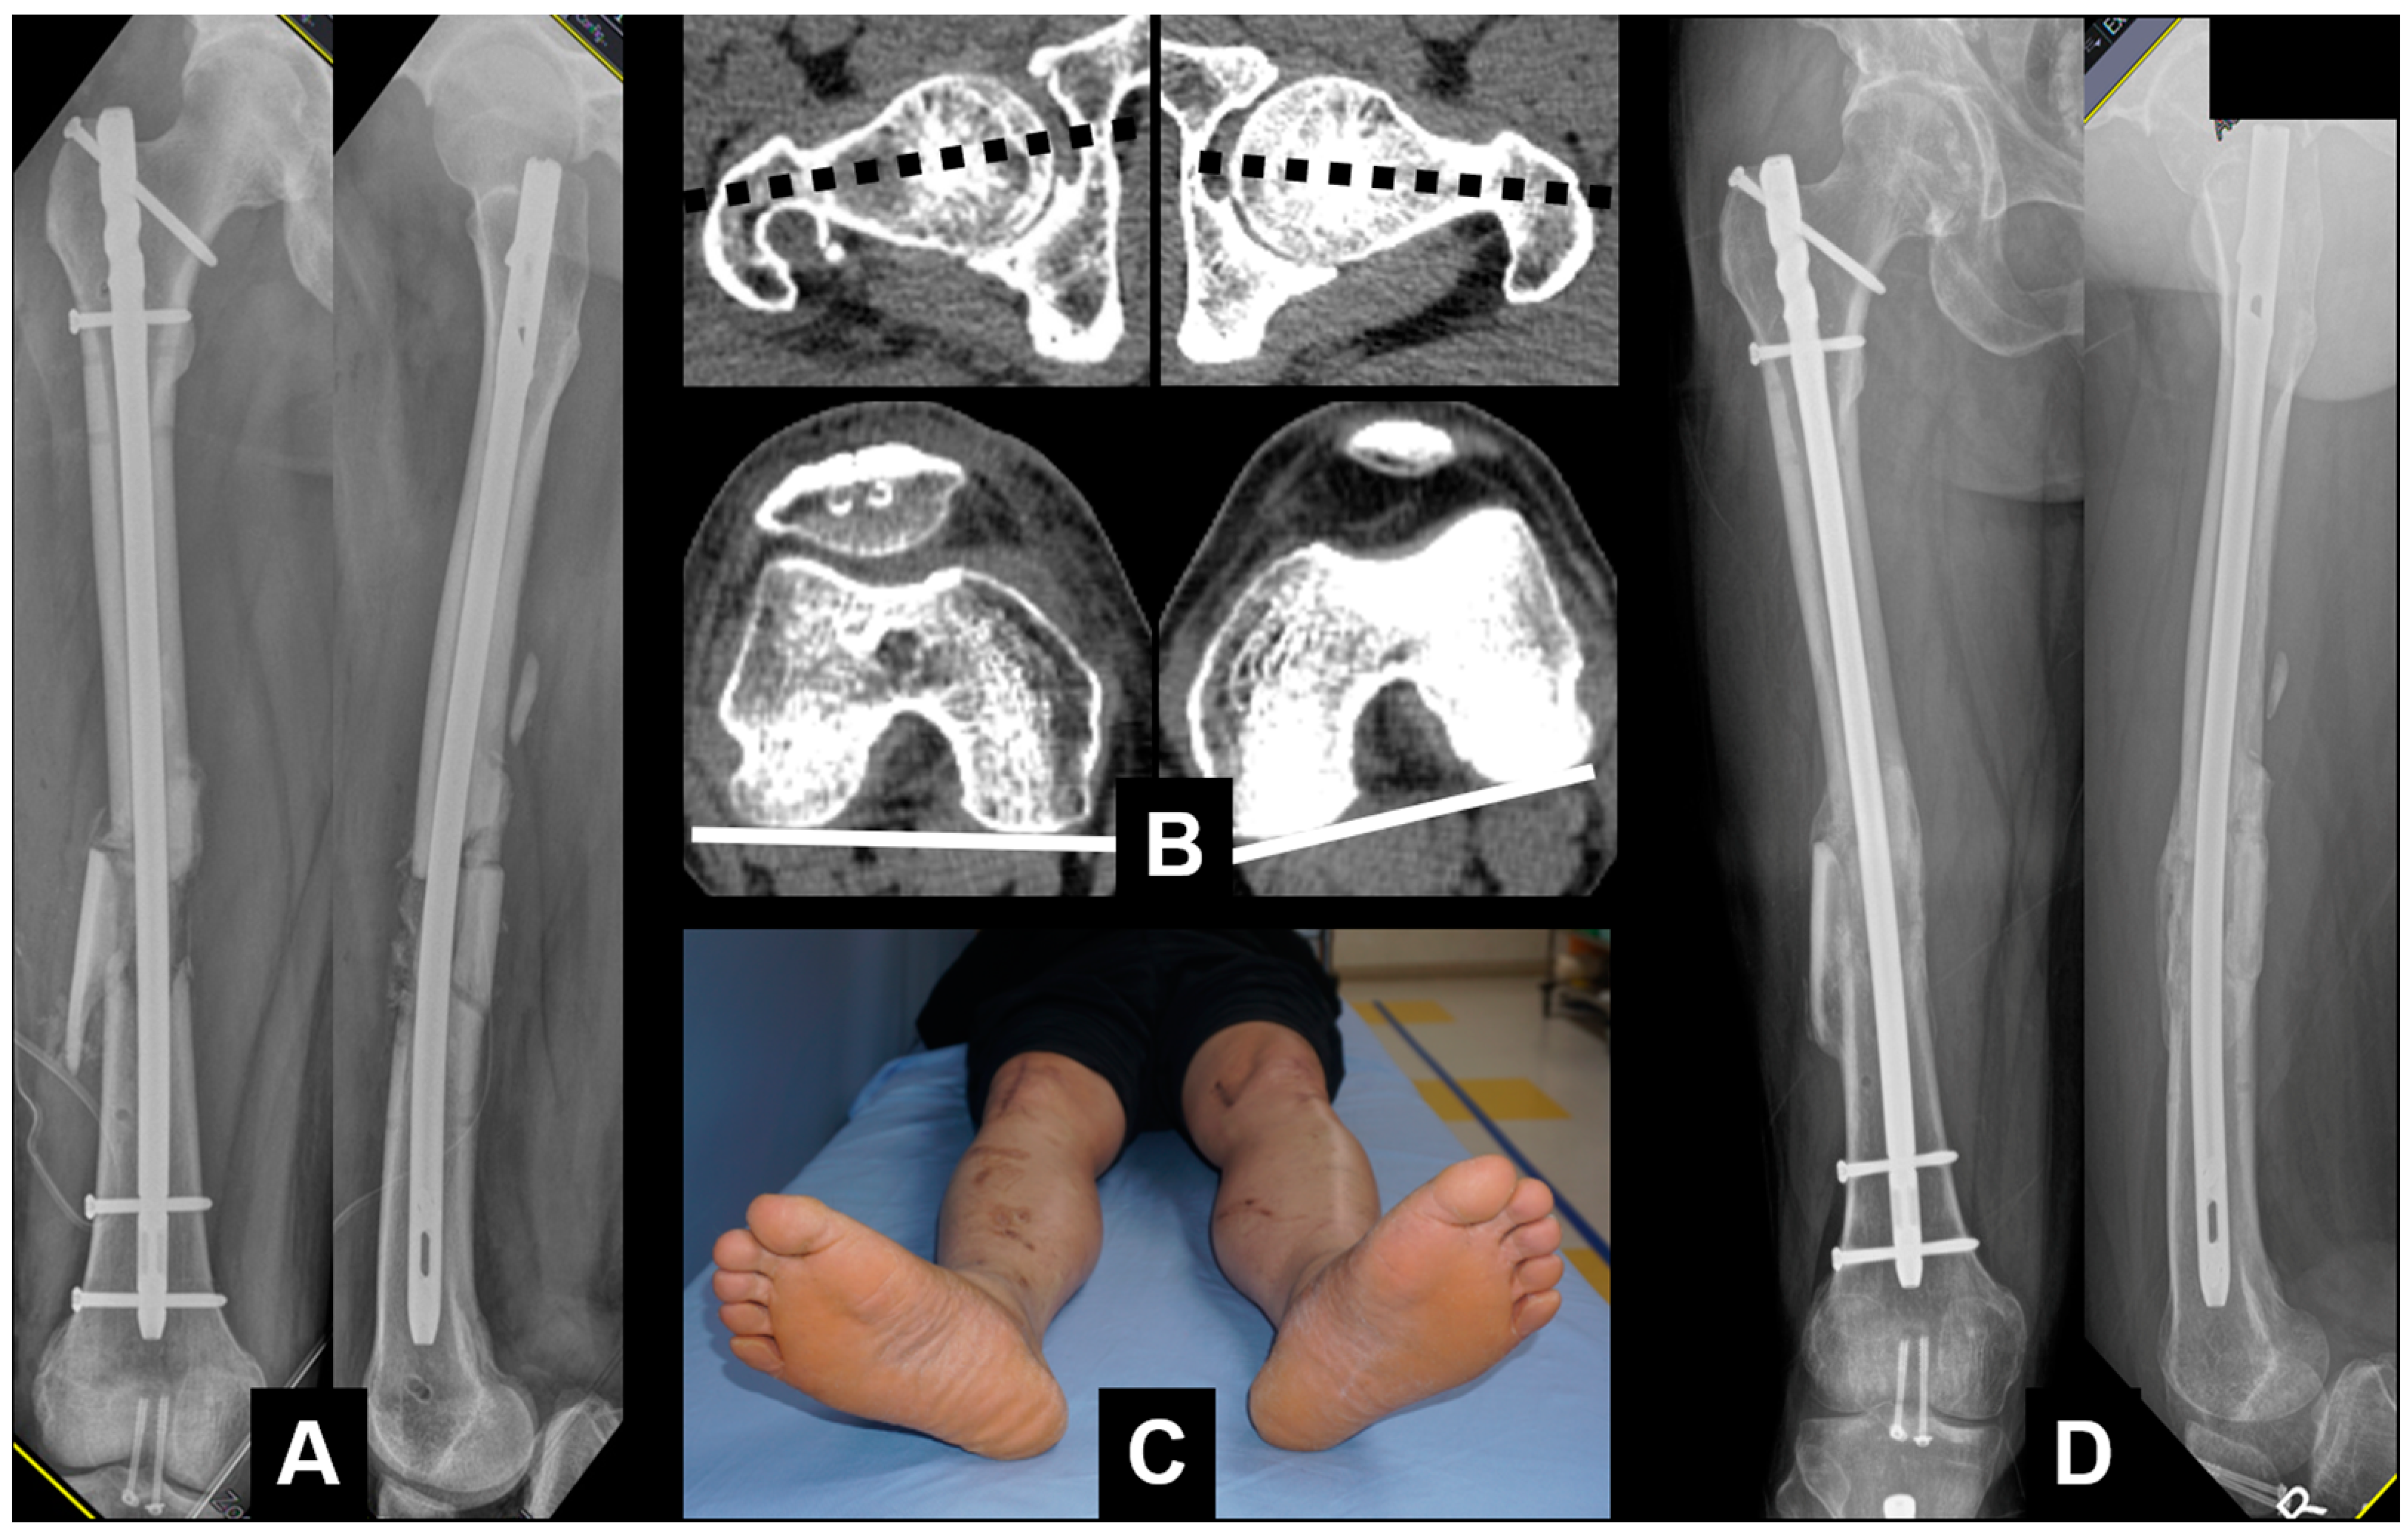

| No. | Sex | Age (Year) | Location | Cause | Rotational Deformity | Associated Deformity | Implant | Bone Graft | Pre- Operative Difference | Angle Measured Using SP App | Post- Operative Difference | Gained Angle | Time to Union (Weeks) |

|---|---|---|---|---|---|---|---|---|---|---|---|---|---|

| 1 | M | 15 | Femur | Malalignment | Internal | Nail | none | 16.1 | 15.8 | 2.3 | 13.8 | 12 | |

| 2 | M | 37 | Femur | Nonunion | External | Nail | YES | 38.3 | 36.1 | 3.2 | 35.1 | 16 | |

| 3 | M | 22 | Femur | Malalignment | External | Nail | none | 22.3 | 20.9 | −1.5 | 23.8 | 16 | |

| 4 | M | 49 | Femur | Malunion | External | Varus | Nail | YES | 15.6 | 14.1 | 1.4 | 14.2 | nonunion |

| 5 | F | 32 | Femur | Nonunion | Internal | Nail | YES | 27.8 | 29.5 | 4.3 | 23.5 | 18 | |

| 6 | M | 50 | Femur | Malunion | Internal | Varus | Plate | none | 20.2 | 20.3 | −2.1 | 22.3 | 16 |

| 7 | M | 57 | Femur | Nonunion | External | Nail | none | 20 | 19.2 | −4.2 | 24.2 | 18 | |

| 8 | M | 70 | Femur | Nonunion | External | Nail | YES | 35.9 | 35.3 | −3.3 | 39.2 | 20 | |

| 9 | M | 57 | Femur | Nonunion | Internal | Nail | YES | 23.5 | 22.2 | 2.5 | 21 | 24 | |

| 10 | M | 58 | Femur | Nonunion | External | Nail | YES | 11.2 | 10.4 | −2.7 | 13.9 | 20 | |

| 11 | M | 46 | Femur | Nonunion | External | Nail | YES | 23.9 | 23.4 | 4.8 | 19.1 | 18 | |

| 12 | M | 11 | Femur | Malalignment | External | Nail | none | 20.6 | 20.1 | −1.6 | 22.2 | 14 | |

| 13 | M | 27 | Femur | Nonunion | Internal | Nail | none | 21.8 | 20.5 | 4.2 | 17.6 | 18 | |

| 14 | M | 24 | Femur | Malunion | Internal | Varus | Nail | none | 17.8 | 19.6 | 3.0 | 14.8 | 16 |

| 15 | F | 15 | Tibia | Malalignment | Internal | Procurvatum | Plate | none | 16.3 | 14.7 | 1.3 | 15 | 14 |

| 16 | M | 77 | Femur | Nonunion | External | Nail | none | 23.1 | 20.2 | 4.6 | 18.5 | 20 | |

| 17 | M | 17 | Femur | Nonunion | External | Nail | YES | 17.2 | 15.9 | 2.5 | 14.7 | 20 | |

| 18 | M | 20 | Tibia | Malunion | External | Nail | none | 30.3 | 32.5 | 1.5 | 28.8 | 20 | |

| 19 | M | 36 | Femur | Nonunion | Internal | Nail | none | 22.1 | 19.3 | −1.8 | 23.9 | 18 | |

| 37.9 | 22.3 | 21.6 | 2.3 | 21.3 | 17.7 |